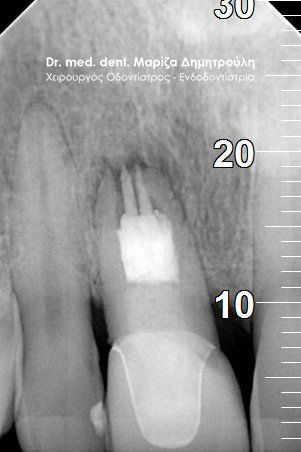

Root canal retreatment

BEFORE